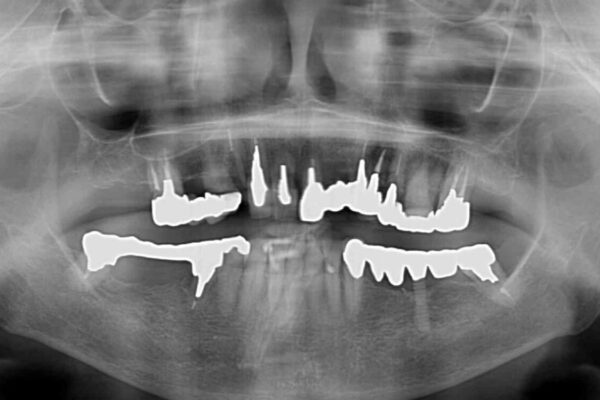

抜歯の必要な前歯や、以前治療した前歯のクラウンの外観を気にして来院された患者様です。

上顎犬歯や下顎大臼歯は、必要なところはインプラントを埋入することとしました。

クラウンが不適合であったり、根管治療の必要なほどの痛みのある歯であったり、見た目の気になる前歯などをオールセラミッククラウンに補綴治療を行うこととしました。

処置を予定していた歯を仮歯に変えた時点で、下顎前歯の部分矯正を行うかどうかを尋ねたところ、折角なので行いたいと言うことでしたので、矯正治療を行うこととしました。

インプラント埋入や根管治療治療など、治癒に一定の期間を要する処置の合間に矯正治療を行うことで、効率的に治療を進めて行くことができました。